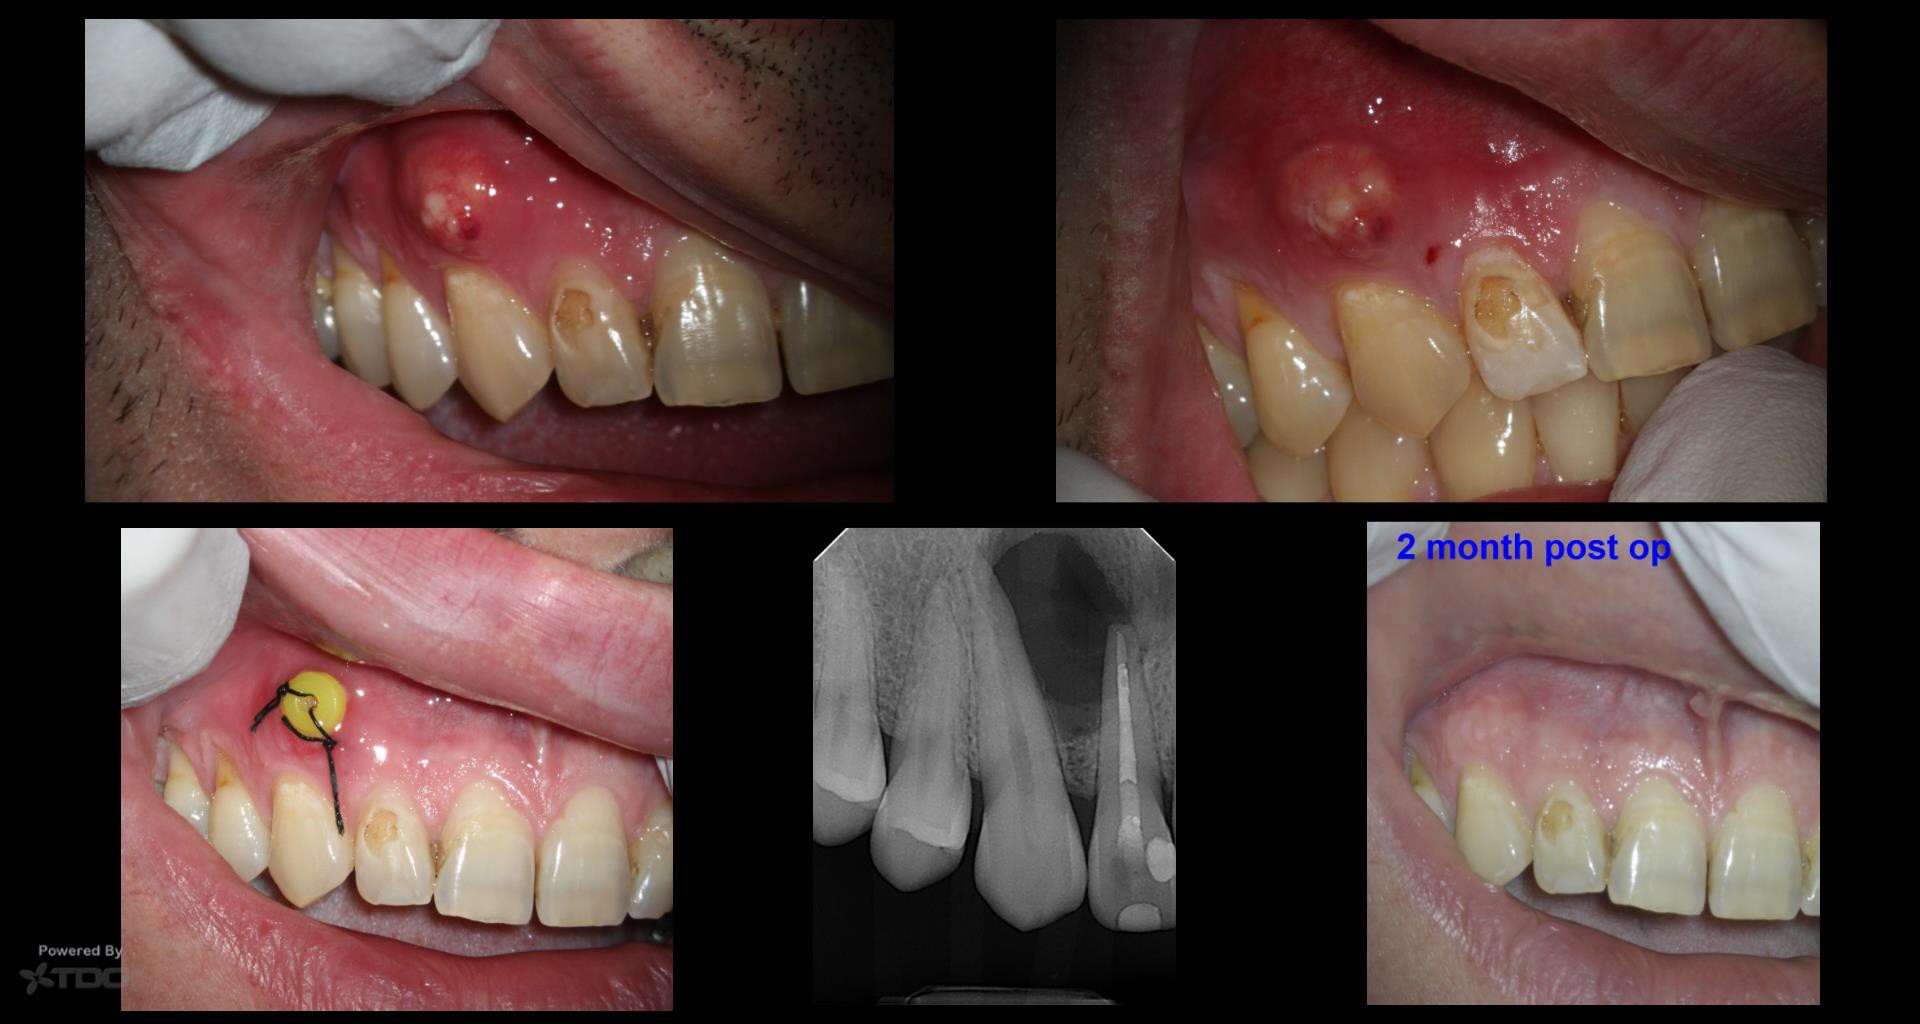

This is a case I treated 1 year ago. It was a “thru and thru”, so I was really not sure how successful treatment would be.

I started with non-surgical endodontics, two visits with CaOH. Pt still returned about 6 weeks later with another buccal swelling. I completed the RCT then and started the decompression with 4-6 weeks rinsing with saline.

Pt was in last week for a follow up and I was surprised to see the bone regeneration on both buccal and palatal cortical plates. My experience with large lesions is that they can take longer than a 2 yr span and as long as he remains completely asymptomatic, we will keep checking on the progress.